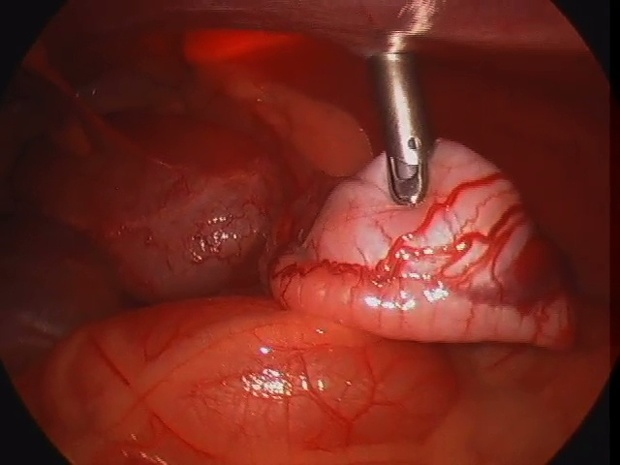

腹腔内臓器の観察

腹腔鏡は肉眼で見ているようにお腹の中を小さな穴から見ることができます。拡大してみているので、肉眼で見ているよりもむしろきれいかもしれません。お腹のなかに何らかの異常が疑われる場合で、レントゲンやエコーでその異常が確認できない場合、腹腔鏡下でお腹の中を観察することができます。